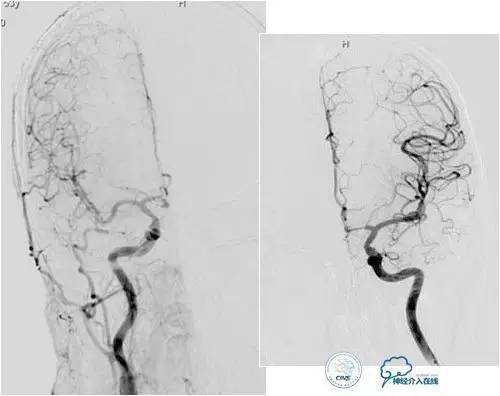

小脑幕缘区DAVF,只有颈外动脉参与供血,供血支细小。

选择抑制血管栓塞,胶无法弥散进入瘘口,选择另一支血管,近端防止Hyperform球囊。

最终胶弥散结果,瘘口完全消失。